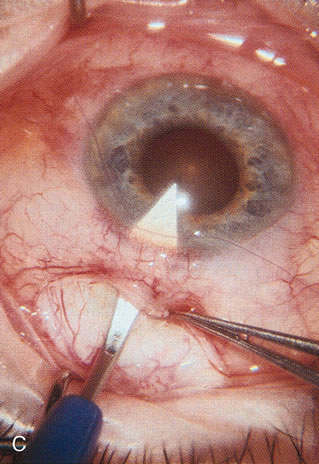

Fig. 3. Partial bleb failure following clear corneal phacoemulsification with foldable IOL. A. Preoperative bleb appearance prior to temporal lens extraction. Preoperative IOP was 12 mm Hg on no antiglaucoma medications. Time from 5-FU trabeculectomy surgery to lens extraction was one year. B. Bleb appearance 2 months after clear corneal cataract surgery with topical anesthesia. Following lens extraction, increased vascularity was noted along with decreased size of the filtering bleb. IOP increased to 20 mm Hg as early as 2 weeks after surgery, necessitating topical antiglaucoma therapy. C. High magnification view of bleb before lens extraction demonstrates diffuse pale bleb. D. High magnification view of bleb 2 months after surgery. There are vessels surrounding the nasal side of the bleb and the overall bleb size is smaller.

Cataract extraction by any technique performed in a patient with a pre-existing filter will have an effect on the previous filtering bleb.121–124 Bleb failure is more likely with ECCE compared with small-incision phacoemulsification.125 However, even patients undergoing topical anesthesia with clear corneal phacoemulsification and foldable IOL may experience bleb failure. One of three patients with a functioning filter and preoperative mean IOP of 12 mm Hg without antiglaucoma medications experiences bleb failure after lens extraction (Table 2). These patients require long-term drug therapy or bleb needling to control IOP. 126 Additional incisional glaucoma surgery may eventually be required in up to 10% of patients.127 Intraoperative iris manipulation may cause significant breakdown of the blood–aqueous barrier, resulting in inflammation that causes bleb failure. Even after uncomplicated clear corneal phacoemulsification, IOP may increase an average of 2 to 3 mm Hg due to bleb fibrosis.128 Approximately 20% of filtered patients require a long-term increase in glaucoma medications following uncomplicated clear corneal phacoemulsification with a foldable copolymer acrylic IOL129 (Fig. 3). In situations in which the bleb is not working at all, the eye will have a postoperative pressure spike that mimics that in the patient not having had a prior filtering procedure. In situations in which the bleb is marginal, the pressure spikes tend to be lower, and the final postoperative IOP tends to be around 50% higher than it was preoperatively. These patients require combined procedures in order to reestablish long-term filtration. In situations in which the bleb is very thin, polycystic, and associated with an IOP around 5 to 8 mm Hg on no antiglaucoma therapy; uncomplicated cataract extraction will have a minimal effect on the level of IOP. Patients with functioning glaucoma drainage implants usually have minimal long-term changes in IOP after uncomplicated cataract extraction.130